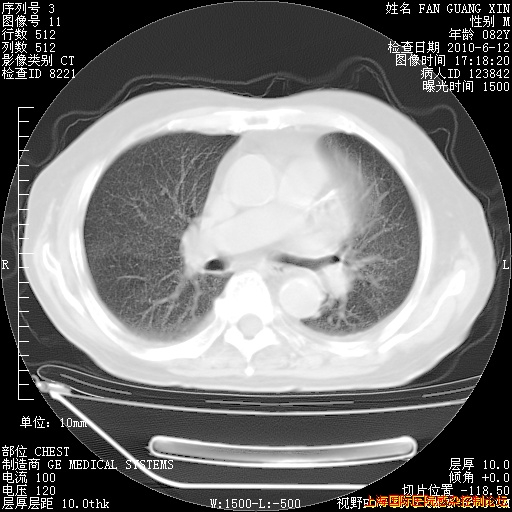

补发6月12日肺部CT肺窗

回复

6月12日肺窗